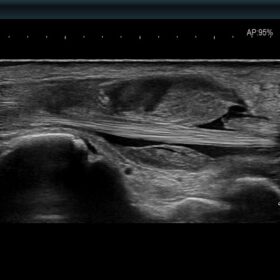

Ultrasound ARIETTA 750 VE – Image Gallery and Videos

Women’s Health

Be equipped for breast pathologies and fetal assessment.

- Highly sensitive colour mode to replace contrast agents

Linear

Hitachi L55 Breast Linear